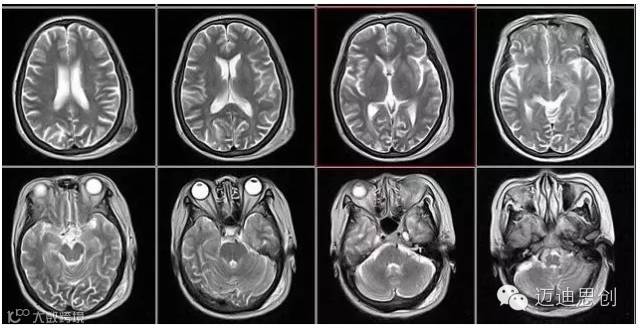

核磁共振:摇一摇再看

核磁共振机使用较强大的磁场,使人体中所有水分子磁场的磁力线方向一致,这时核磁共振机的磁场突然消失,身体中水分子的磁力线方向,突然恢复到原来随意排列的状态。简单说就相当于用手摇一摇,让水分子振动起来,再平静下来,感受一下里面的振动。所以,核磁共振(MRI)也被戏说为是摇摇看的检查。

2、颈椎腰椎——最佳选核磁、次选CT

颈椎病、腰椎间盘突出等椎间盘疾病需要观察椎间盘与相应的神经根,要想更好观察这些软组织,最优选择就是核磁。同样,对于关节、肌肉、脂肪组织检查,核磁也是首选。